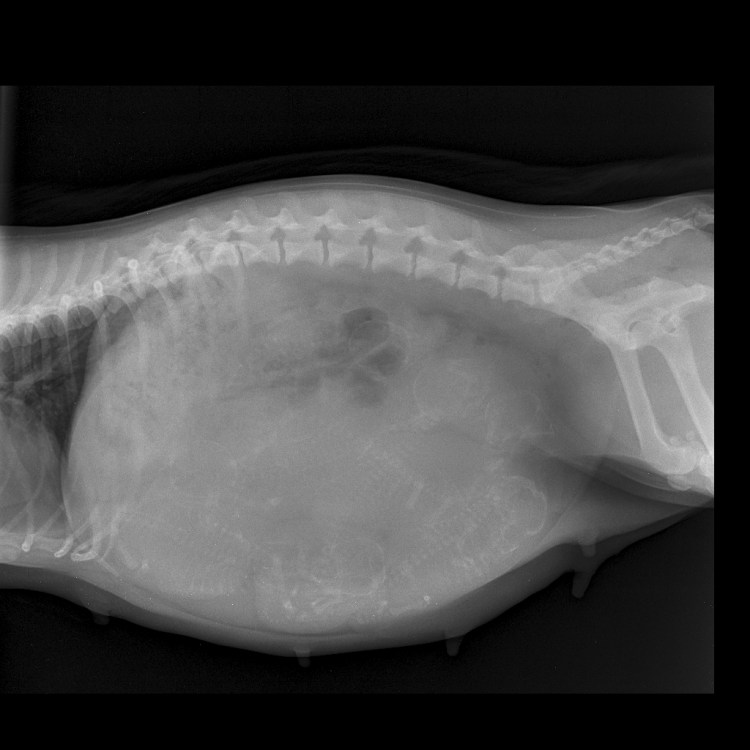

Xray of puppies whilst in the womb